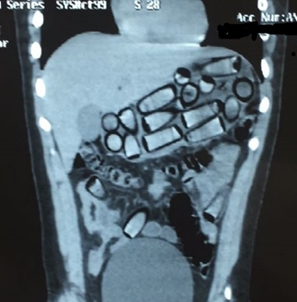

Radiológicamente se puede observar la presencia de objetos o cuerpos extraños radiopacos redondeados u ovalados en el tracto intestinal y se puede ver el "signo de la roseta" o imagen formada por el aire atrapado en el nudo del preservativo y el "signo del doble preservativo, o imagen formada por el aire atrapado entre las capas de látex, que los hacen más visibles. Hay que tener mucha acuciosidad de observar desde el estómago hasta el recto. (7). La tomografía computada, además de observarse las capsulas o cuerpos extraños se puede revelar ocupando el marco colónico casi por completo, con irregularidad en sus contornos, presentado el signo del «jigsaw» o rompecabezas, que ha sido reportado en la literatura y que se origina como producto de láminas de aire intestinal entre el empaquetado y el mesenterio (8)(10).

Se trae a discusión un paciente, de sexo masculino 37 años de edad, nacionalidad extranjera, que ingresa a un hospital público de tercer nivel asintomático, traído por servidores policiales, al ser encontrado en un aeropuerto rumbo a Europa, detectándose por la negativa a ser revisado y nerviosismo a realizar el interrogatorio. Se realizó exámenes de control, radiografía para comprobar la presencia del cuerpo extraño tipo capsulas, ovaladas, luego se realiza una tomografía simple para observar la distancia del recorrido de las capsulas de droga.

Ilustración 2 TAC Presencia de capsulas cocaína

Fuente: Hospital de Especialidades Guayaquil “Doctor Abel Gilbert Pontón”.

Autor: Dr. Fernando Moncayo A.